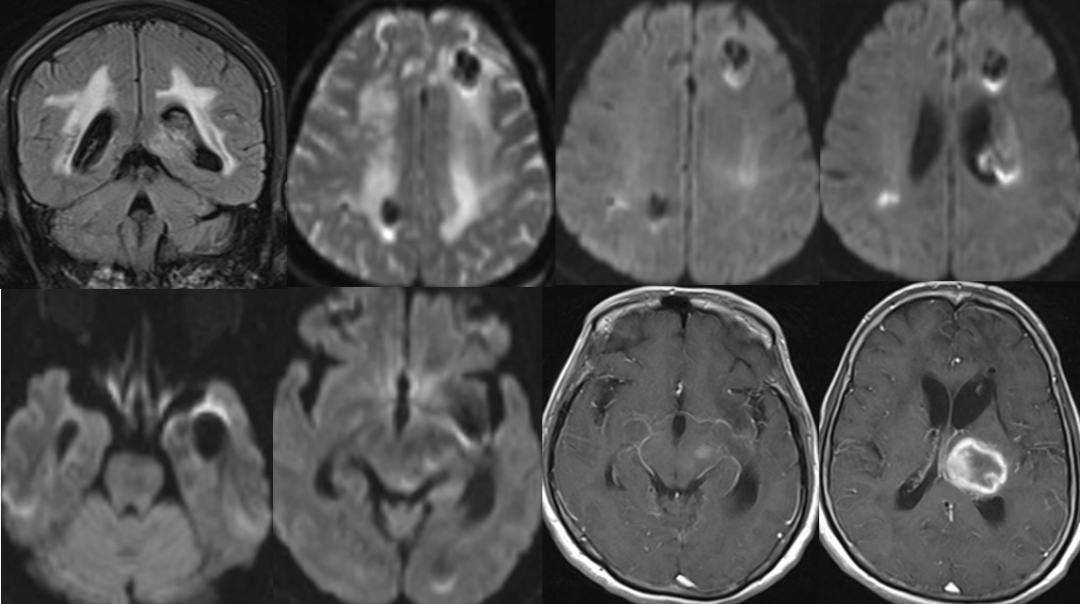

脑干梗塞?

2014-11-27 MRI

2014-11-27 CT

渗透性脱髓鞘综合征?

渗透性脱髓鞘综合征(osmotic demyelination syndrome,ODS)

是一种少见的急性非炎性中枢脱髓鞘性疾病,主要是由于慢性低钠血症时脑细胞已经适应了一种低渗状态,此时一旦给予迅速补钠,血浆渗透压迅速升高造成脑组织脱水而继发脱髓鞘。

分为脑桥中央髓鞘溶解症(central pontine myelinolysis, CPM),脑桥外髓鞘溶解症(extrapontine myelinolysis, EPM)。

CPM表现为四肢瘫和不同程度的脑干功能障碍,如假性延髓麻痹,偶有闭锁综合征、缄默症。EPM主要表现为运动障碍、肌张力障碍、帕金森综合征等,仅出现小脑体征者罕见。

影像学特征

CT表现为脑桥中央或脑桥外病灶处的低密度影。

MRI能更好地反映病灶的数量和程度。早期可无异常,出现症状后1周DWI上可发现高信号。急性期表现为对称的T1WI低信号,亚急性期可能是由于内皮细胞受损所致的微出血而显示T2WI高信号。FLAIR显示病灶高信号更清楚,能更好地显示临近脑脊液的病灶,比如大脑皮质,应作为常规检查。也有一些报道发现皮质层及皮质下T1高信号,有的钆增强被强化,有的不被强化。脑MRI对本病具有十分重要的诊断意义,大约在发病2~3周时异常信号最为明显,所以结合病史及临床表现如果考虑ODS的诊断,在MRI检查正常的情况下,在出现症状后10~14天复查MRI是十分重要和必要的。